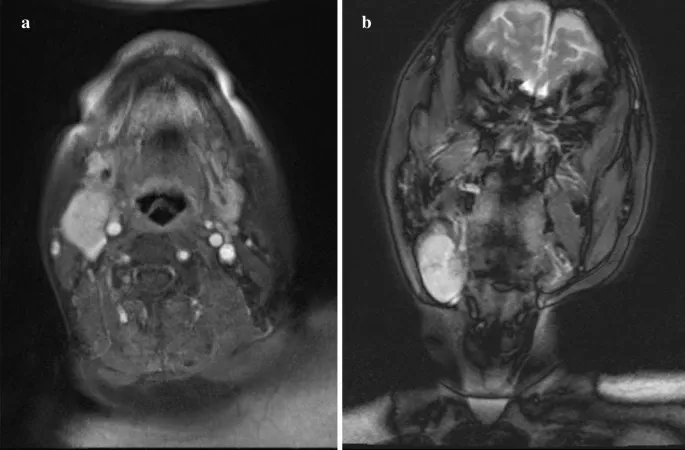

初诊时,右侧下颌下区可触及一个40×30 mm、弹性柔软、可移动的肿块,边界清晰,皮肤颜色健康。无自发性疼痛和压痛。MRI示圆形肿块,边界较清晰,大小为29×24×40 mm,前缘毗邻右侧颌下腺,后深部压迫右侧颈内静脉。边缘很光滑。肿块表现出高信号强度区域,部分伴随为内部的低信号区域。周围组织未见浸润,未见其他明显肿大淋巴结。基于这些发现,强烈怀疑涎腺肿瘤(图1a, b)。

图1. MRI的发现